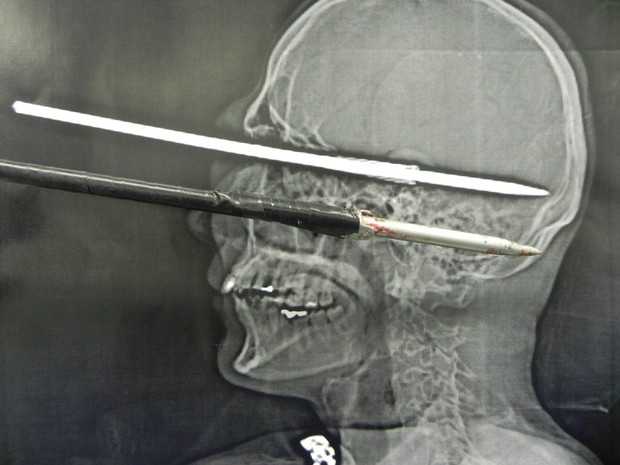

| Hình ảnh cây xiên cá đâm xuyên qua hộp sọ bệnh nhân. |